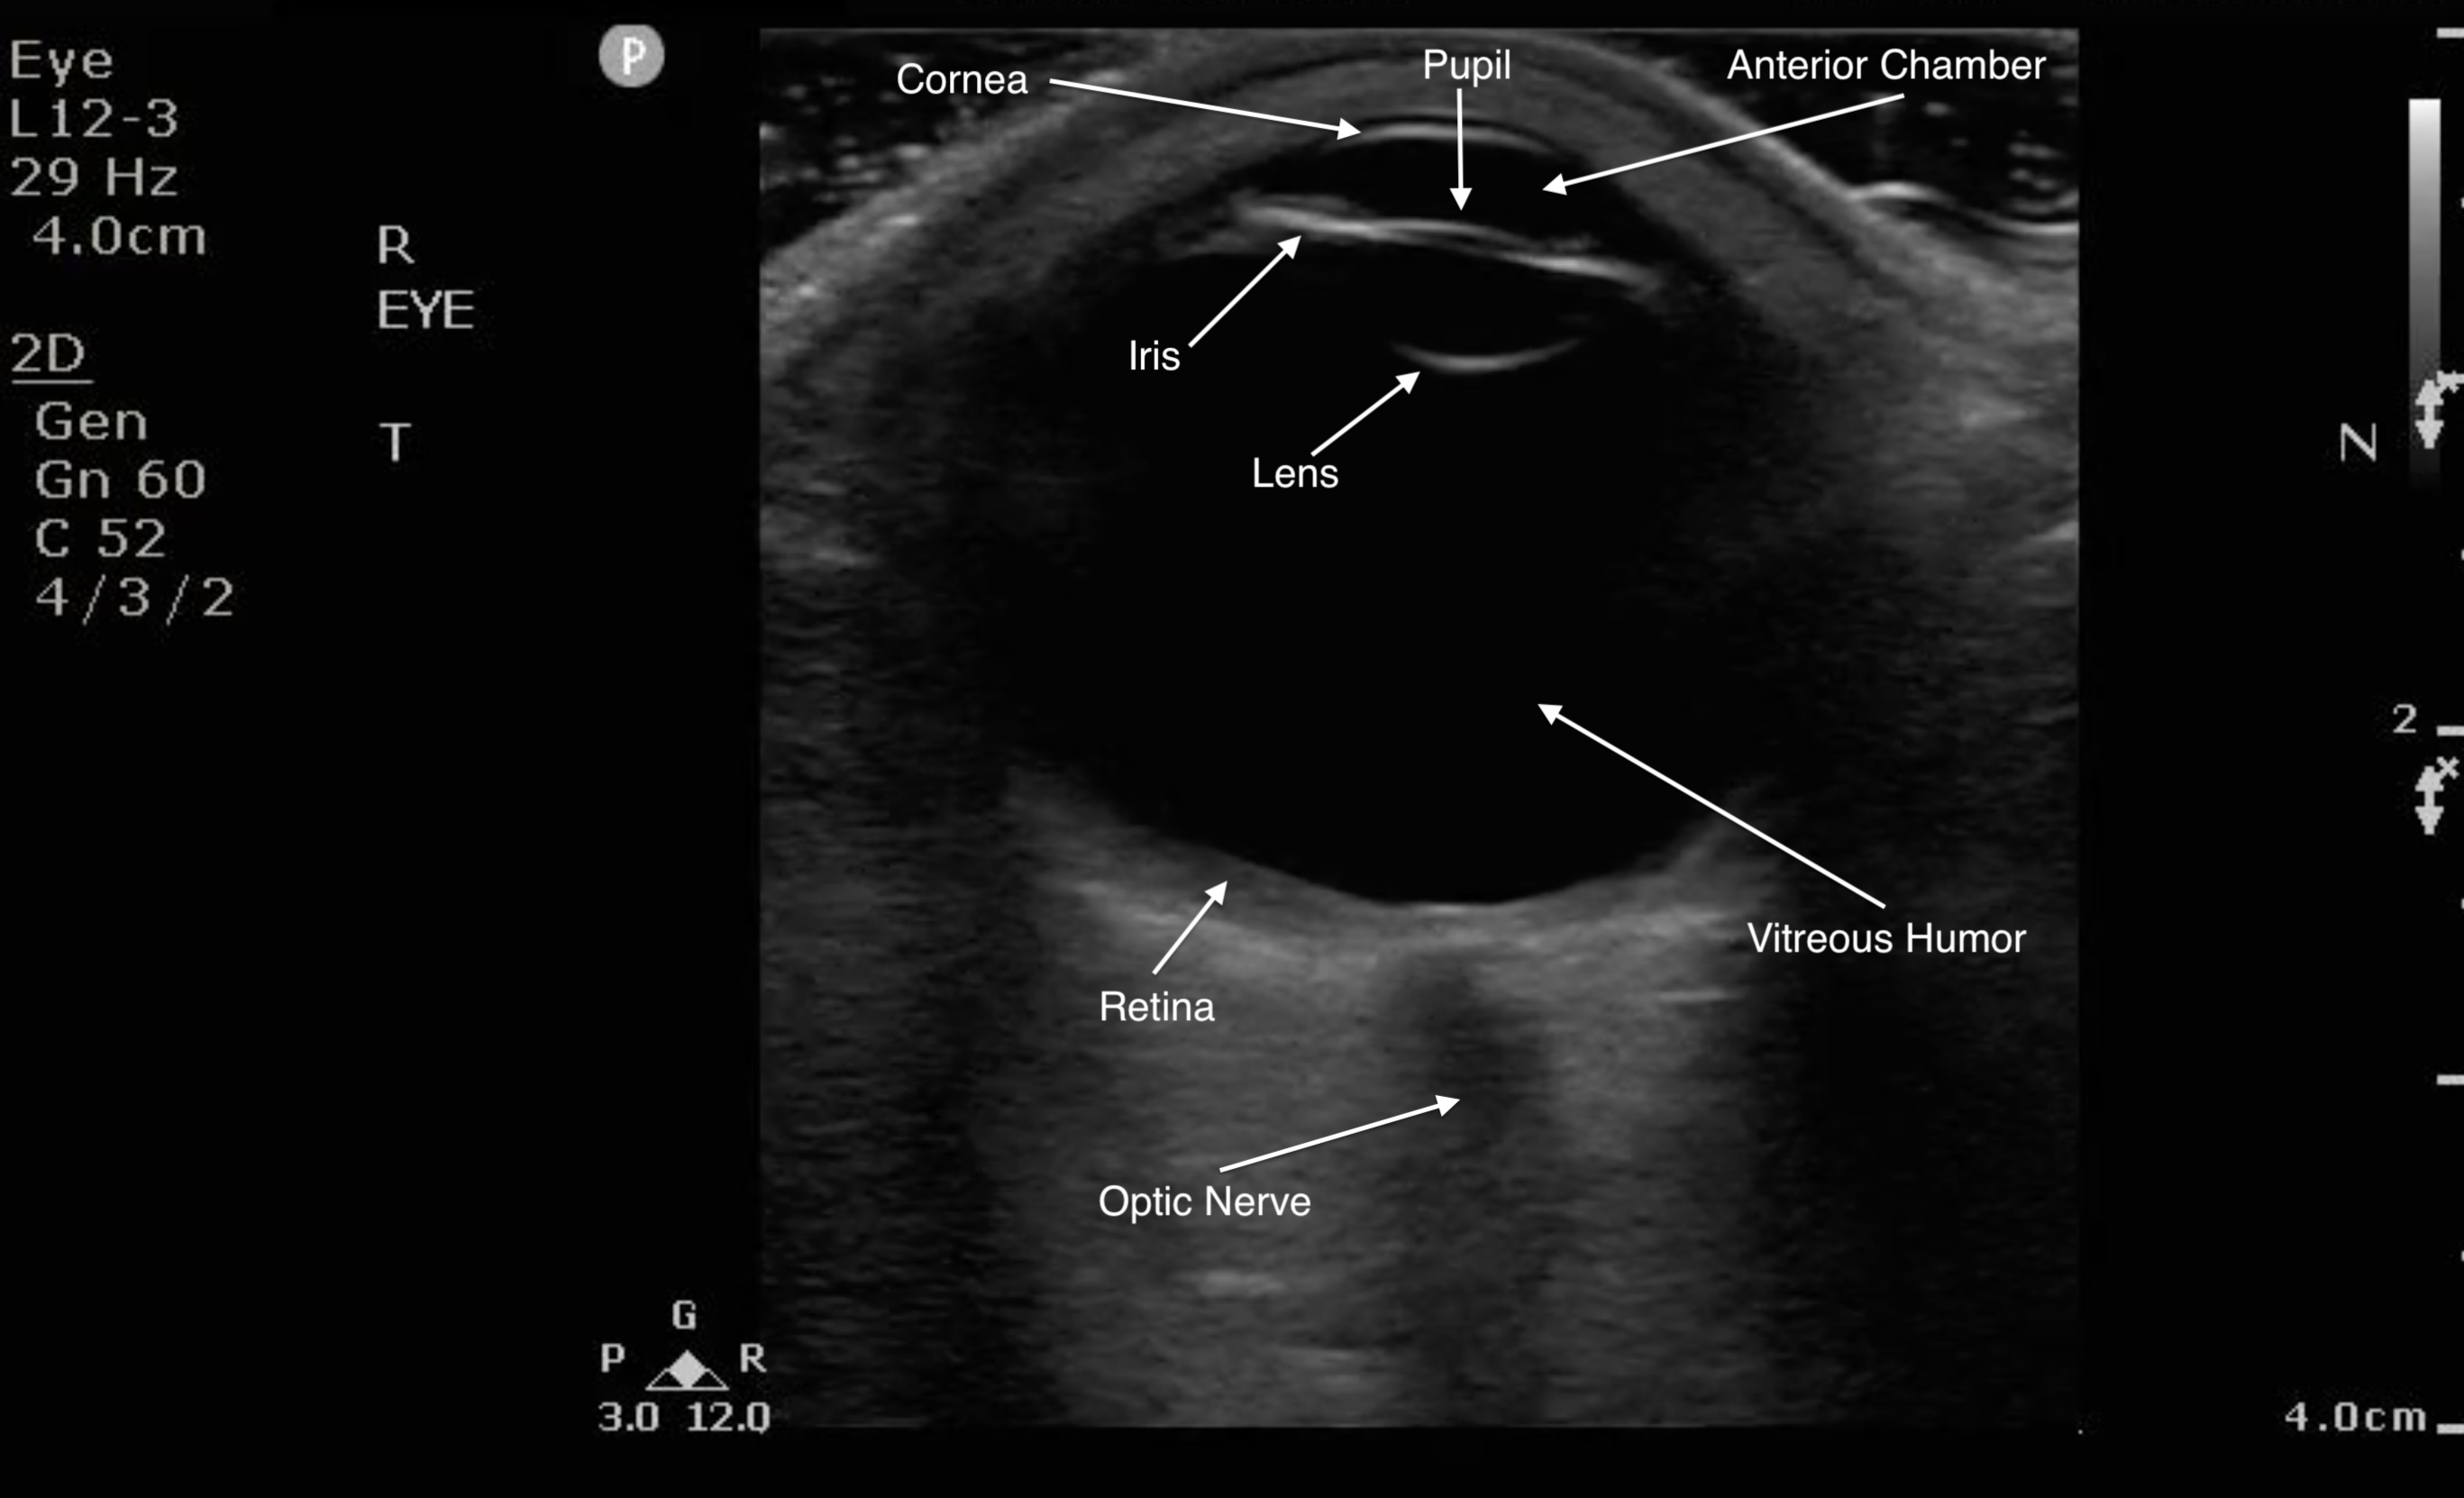

Figure 1. Sonographic eye anatomy

Normal Findings

- Because the ocular chamber is fluid-filled, under ultrasound, it will appear as a round, anechoic structure.

- The most anterior structure seen, after the layer of ultrasound gel, is the eyelid.

- Just deep to the eyelid is the cornea and the anterior chamber. If too much pressure is applied during the ocular ultrasound examination, the anterior chamber may become compressed. It is important to avoid applying direct pressure to the eyelid.

- If the patient attempts to look down during the exam, you may be able to visualize the iris and pupil.

- The lens appears as a hyperechoic, curved line, located deep to the iris. If the patient has undergone cataract surgery, you may see two thin, hyperechoic parallel lines instead of the concave hyperechoic line.

- Normal vitreous humor will appear anechoic.

- The vitreous, retina, and choroid are located along the inside of the globe. Normally, you cannot differentiate one from the other.

- The most far field identifiable structure is the optic nerve. The parallel hyperechoic lines are the optic nerve sheath, since the optic nerve is hypoechoic and nondistinctive.

- Figure 3. Ultrasound image of a normal eye.